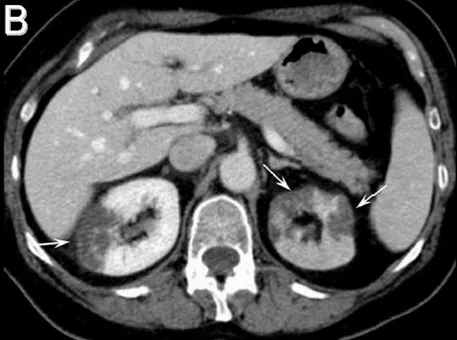

IRA + Icterícia: Um Caso que Exige Investigação Detalhada